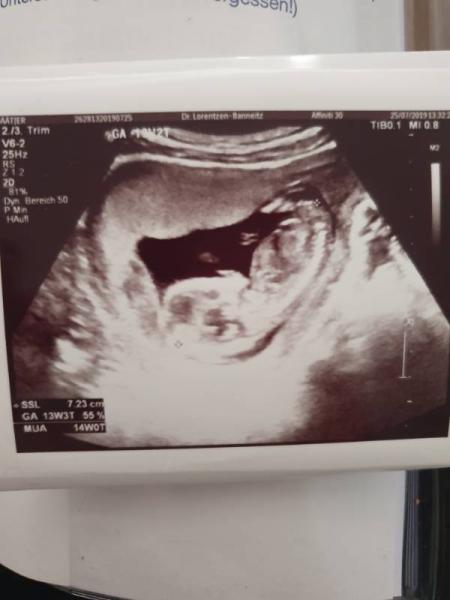

Hallo ihr Lieben, ich melde mich auch mal wieder.. habe die 14. Woche erreicht und dem zwergi geht es super und ist prima gewachsen beim letzten US Termin am Donnerstag hat meine FA gesehen das die Nackenfalte fast komplett weg und negativ ist .. jetzt heißt es wieder 4 ganze Wochen warten und hoffen das es sich dann zeigt was es wird.. ich bin so ungeduldig .. anbei noch ein Foto vom zwergi wünsche euch ein schönes Wochenende und hoffe ihr übersteht die Hitze

Bild zu 14.Woche - Forum für Januar - Mamis

Oh wie schön Wenn ich diese Fotos sehe, wundere ich mich, warum wir noch nix spüren. Das Füßchen deines Kleinen liegt ja direkt an der Gebärmutterwand .